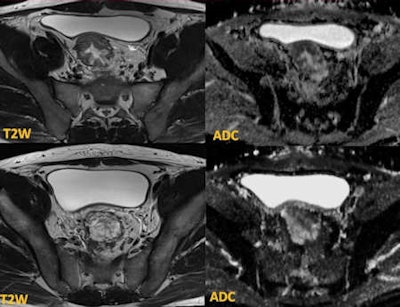

The initial biopsies showed tubulovillous adenoma with no invasion. MRI demonstrates tumor in the sigmoid (upper row) with restricted diffusion. The lower row of images at the rectosigmoid shows T2 high-signal lesion with T2 shine-through effect on the apparent diffusion coefficient (ADC) map -- tubulovillous adenoma. Targeted biopsies confirmed adenocarcinoma, and the patient required chemotherapy before surgery.The important prognostic factors in rectal cancer management -- such as depth of extramural invasion (T staging), presence of lymph node metastases, vascular invasion, and involvement of the circumferential resection margin -- can be accurately assessed on MRI. These factors dictate preoperative management through intense chemoradiotherapy. MRI is also very useful in staging locally advanced rectal tumor (T4 disease), such as the tumor invading the peritoneal reflection and adjacent pelvic organs. In addition, MRI is routinely used in assessing the tumor response to preoperative chemoradiotherapy.